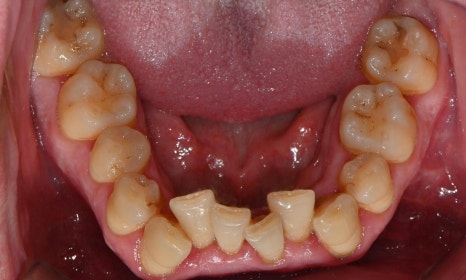

진단 결과, 교합시 하악 전치가 거의 보이지 않을 정도로 깊은 교합을 보이고 있었으며, 어린 시절 외상을 입었던 앞니는 치아 뿌리 부근에 광범위한 염증이 관찰되어 장기적인 유지가 어려운 상태였습니다. 이에 앞니 두 개는 발치를 결정하였고, 환자의 비교적 젊은 나이를 고려하여 가능한 한 최대한 치아를 보존하기 위해 앞니 부위 임플란트를 고려했습니다. 그러나 해당 부위 골 손실이 매우 심했고, 외국인 환자로 장기간 내원이 어려운 상황이었기 때문에, 광범위한 골이식을 동반한 임플란트 치료 보다는 비교적 짧은 기간 내에 기능과 심미를 회복할 수 있는 브릿지 보철 치료를 계획하였습니다.

또한 하악 전치가 혀 쪽으로 과도하게 쓰러져 있어 보철적으로 위치를 회복하기에는 한계가 있어, 발치 후 후 상하악 모두 브릿지 보철로 치료 계획을 수립하였습니다. 하악 전치를 원래 자리에 위치시킬 경우 뼈가 너무 올라와 있었기 때문에, 발치 후 아래 앞니 부위 골성형도 시행하기로 하였습니다.